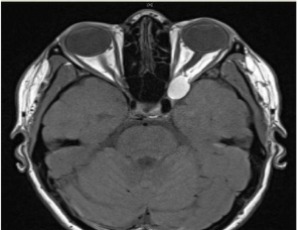

An atypical case of compressive optic neuropathy and cranial nerve 6th palsy caused by a cholesterol granuloma

In this case report we present an unusual case of orbital cholesterol granuloma associated with compressive optic neuropathy and cranial nerve 6th palsy. Cholesterol granuloma results from a foreign body response to the presence of crystallized cholesterol. Cholesterol granuloma affecting the orbit are a rare presentation as they typically occur in the petrous apex of the temporal bone.